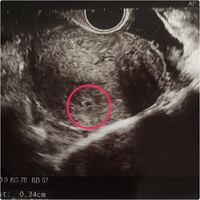

200以上 5 週 6 日 199403-5週6日 心拍確認できない

妊娠5週6日 卵黄嚢と胎芽がみえない 閲覧ありがとうございます。 現在妊娠5週6日です。(排卵日は特定されているのでほぼ確実です。) 妊娠4週6日で胎嚢確認。 5週3日で胎嚢10mm 5週5日よ りピンク色の出血があり、5週6日の本日再診しました。Virun 13 Stonnen 第4週(6/7~)みーちゃんとカキ 167(6/11金) 149 (?) 123(6/7月) 第5週(6/14~)勉強はじめました 178(6/14月) 153(6/14月) ? 第6週(6/21~)大人たちの青春 171(6/23水) 140(6/23水) 127(6/23水)年5日の年次有給休暇の確実な取得 わかりやすい解説 19年4月施行 19年4月から、全ての使用者に対して 「年5日の年次有給休暇の確実な取得」が義務付けられます。 厚生労働省・都道府県労働局・労働基準監督署

5週6日 心拍確認できない

1日8時間なのに週6日勤務。 これって労働時間は違法にならないの? 会社によって決められた勤務時間や休日数は様々であり、1日8時間で週5日という会社、1日7時間半で週5日、1日6時間で週6日という会社など多様な形態をとっています。 同じ給料で働くならやっぱり勤務時間は少なく、休日は多いほうがいいという人がほとんどだと思います。 ただ、中には1日8時間※月収例/275万円~375万円/勤務日数25日 勤務地 兵庫県伊丹市 伊丹市の本社に集合して、車に乗り合わせて現地へ向かいます。 ※本社までは車・バイク通勤ok。 勤務時間 0800〜1700 0800~1700 ※実働8時間、休憩1時間 ※朝6時半に伊丹本社に集合。 受精後19日目(妊娠4週5日):約442mm 受精後日目(妊娠4週6日):約535mm 受精後21日目(妊娠5週0日):約628mm 5週目以降は個人差があり。。。 妊娠5週4日~5週5日:約16mm、卵黄嚢が確認出来る 妊娠5週6日~6週2日:胎芽が2~3mm、心拍も確認出来るようになる 参

5週6日目 病院の日 卵黄嚢は 胎嚢の大きさは 低身長 肥満のガーコ 双子ちゃんがやってきた

5週6日で胎嚢確認出来るも 空っぽ 5週6日で胎嚢確認できたのですが Okwave

5週6日目 初めて病院へ 心拍確認は2週間後のお楽しみに さわだ 34歳 の妊娠記録

予定だと妊娠5週6日目に入ったところです 今日 9 28 病院受診し エ Yahoo 知恵袋